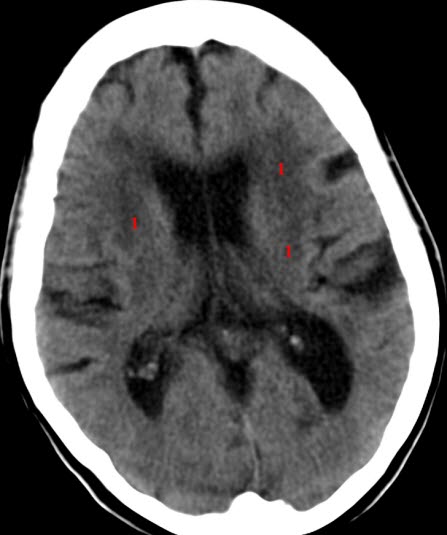

Cerebrale multiinfarkt

CT axialbilde uten kontrast

Uregelmessige, stort sett symmetriske, lavattenuerende (mørke) områder (1) på begge sider med vevstap på grunn av nedsatt blodtilførsel